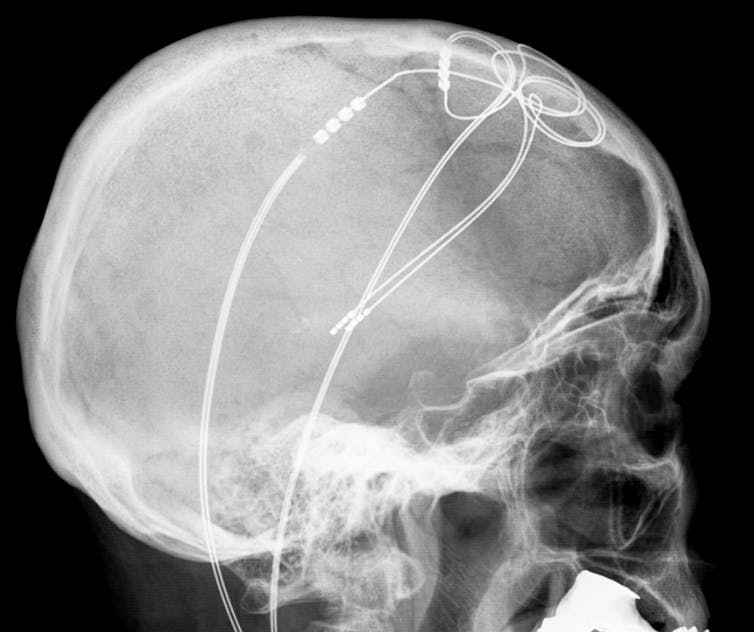

The link between the two? Both Mr. B and Mr. X received deep brain stimulation (DBS), a procedure involving an implant that sends electric impulses to specific targets in the brain to alter neural activity. While brain implants aim to treat neural dysfunction, cases like these demonstrate that they may influence an individual’s perception of the world and behavior in undesired ways.

Mr. B received DBS as treatment for his severe obsessive compulsive disorder. He’d never been a music lover until, under DBS, he developed a distinct and entirely new music preference for Johnny Cash. When the device was turned off, the preference disappeared.

Mr. X, an epilepsy patient, received DBS as part of an investigation to locate the origin of his seizures. During DBS, he hallucinated that doctors became chefs with aprons before the stimulation ended and the scene faded.

In both of these real-world cases, DBS clearly triggered the changed perception. And that introduces a host of thorny questions. As neurotechnologies like this become more common, the behaviors of people with DBS and other kinds of brain implants might challenge current societal views on responsibility.